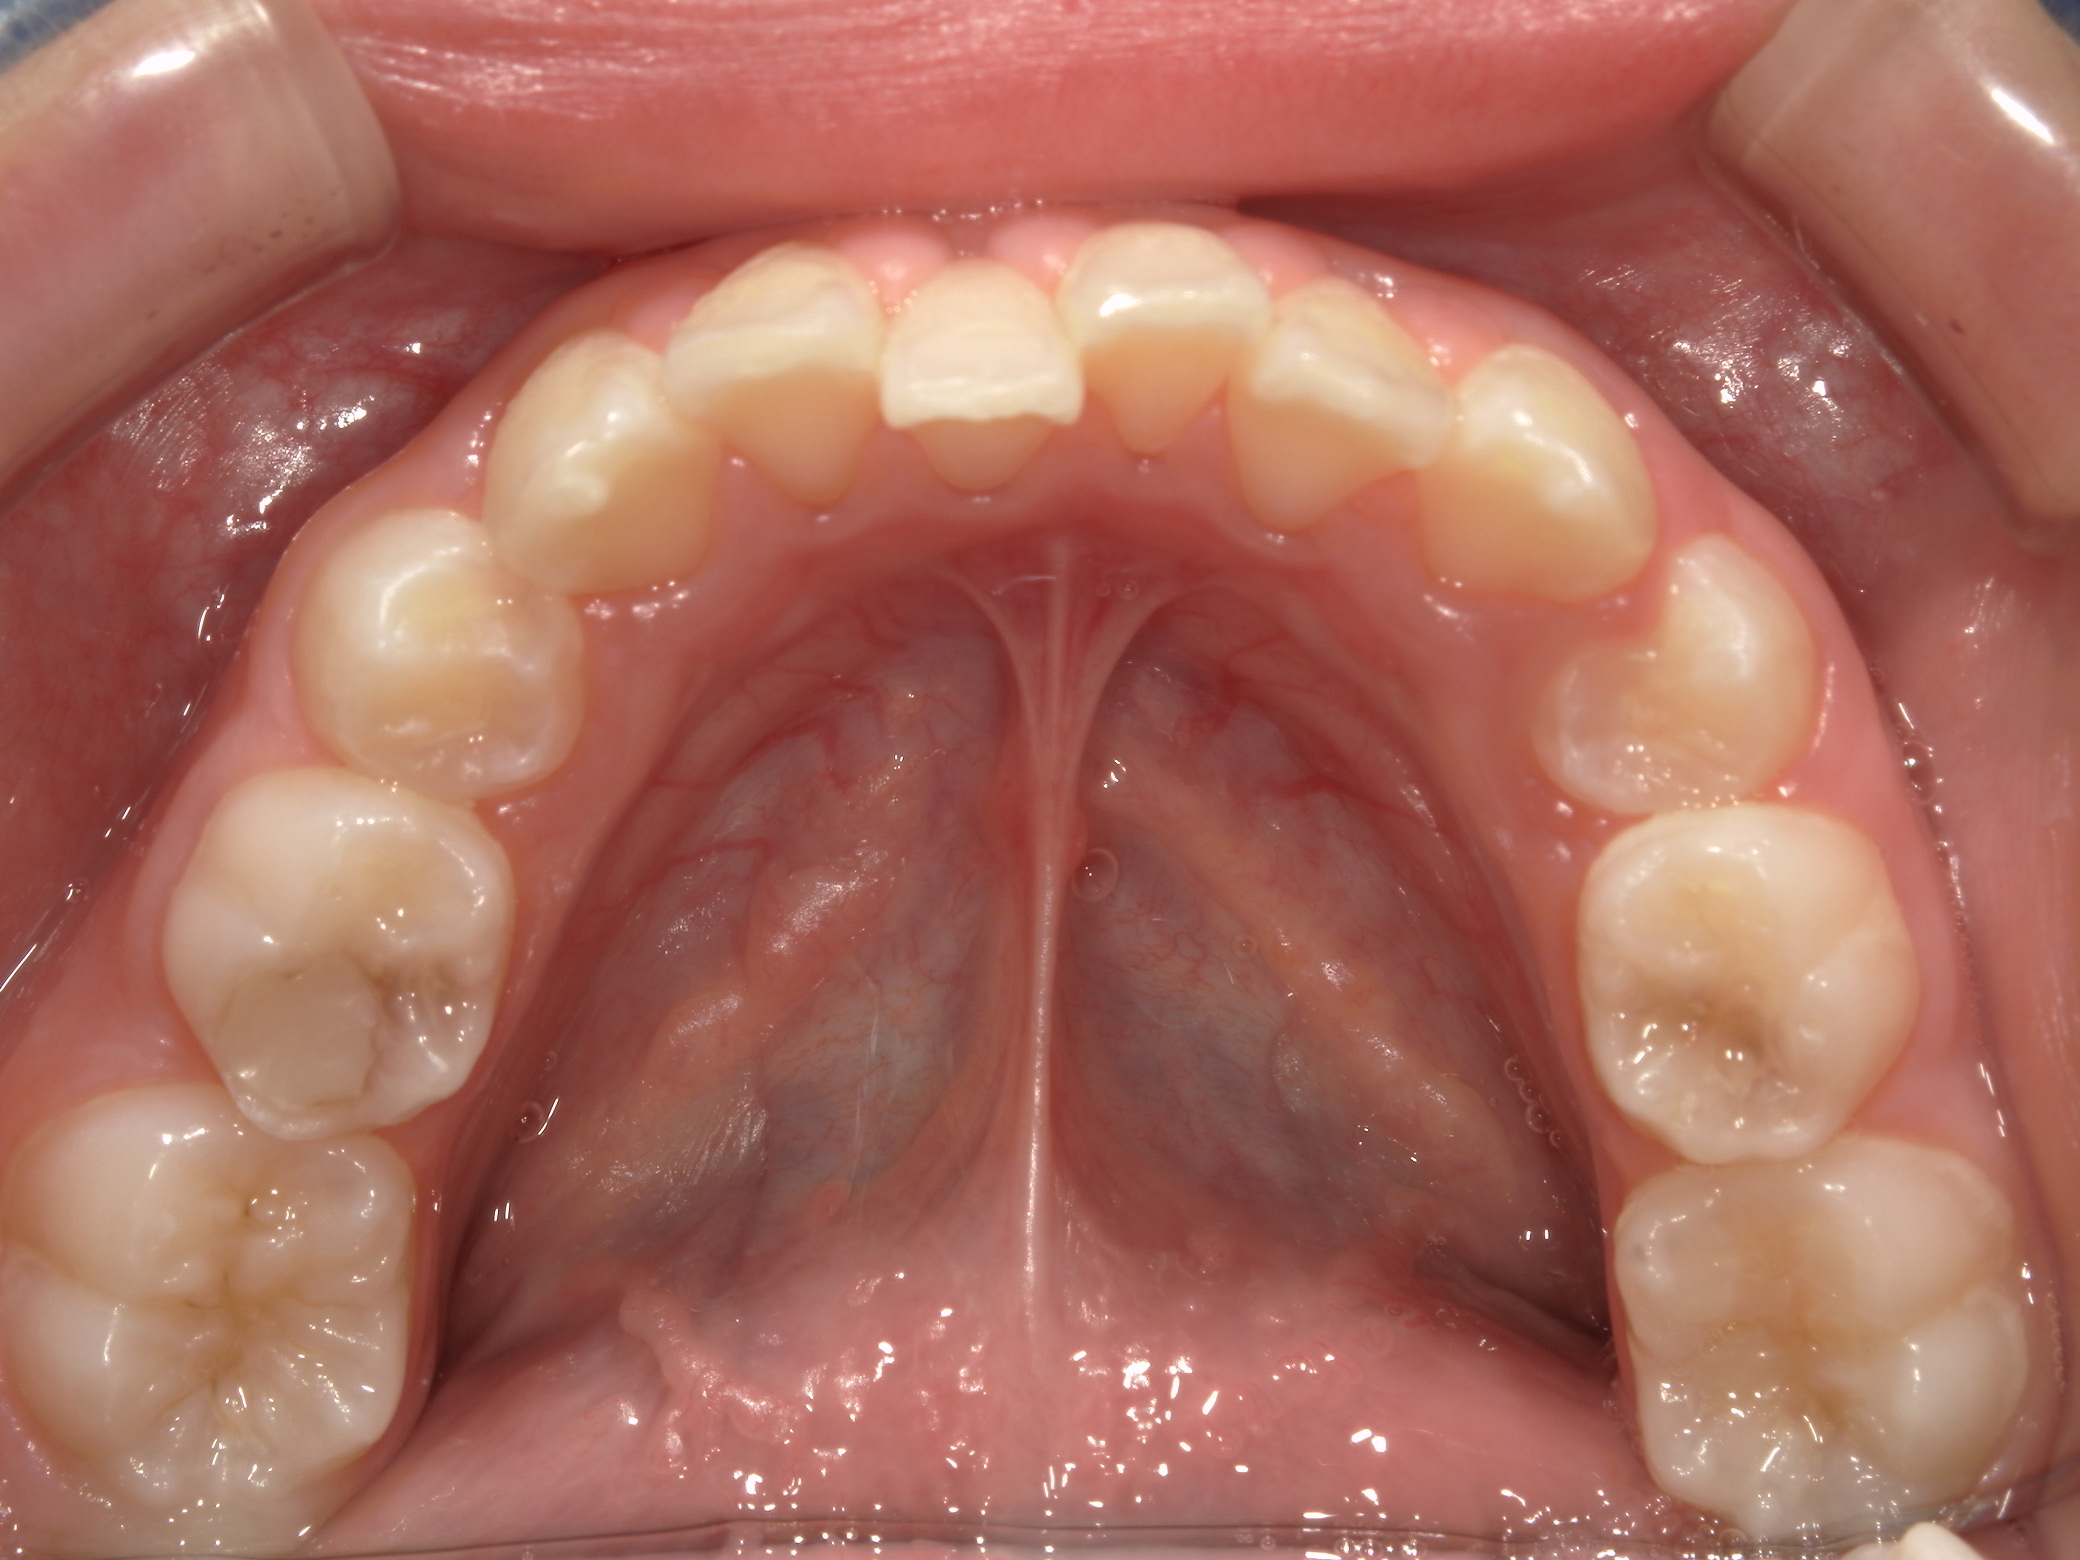

| 年齢・性別 | 8歳9ヶ月の女児 |

|---|---|

| 主訴 | 歯並びの乱れを気にされて来院された患者様です。将来的なスペース不足と歯のねじれ(翼状捻転)が懸念されました。 |

| 治療期間・回数 | 2年10ヶ月・19回 |

| 費用 | 430,000円(税別) |